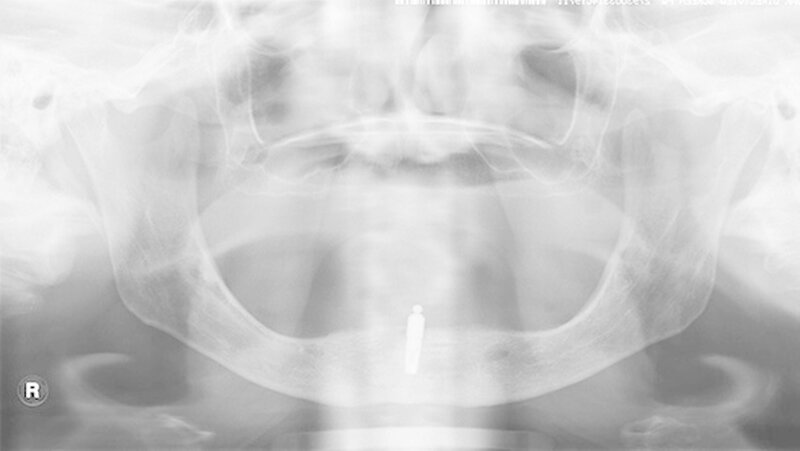

Beispiele für individuellen ZE

Die Jahrestagung der Deutschen Gesellschaft für Prothetische Zahnmedizin und Biomaterialien (PGPro) in Ulm geht der Frage nach, welche Versorgungskonzepte - mit guten Langzeitergebnissen - individuell und preiswert machbar sind. Gute Beispiele finden Sie in unserer Bilderstrecke!